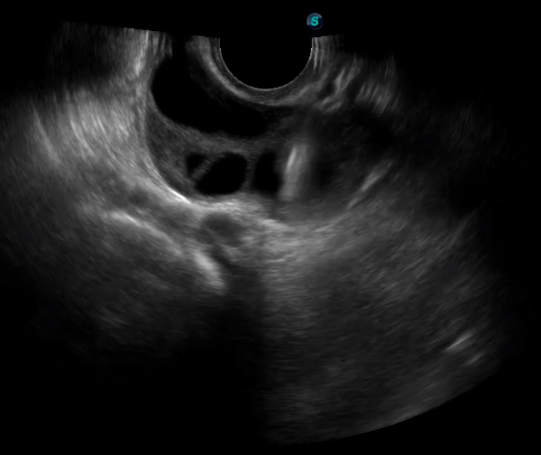

傳統(tǒng)腔內(nèi)探頭采用直柄設(shè)計(jì),在搭配穿刺架使用時(shí),手術(shù)空間小,不易操作;生殖專(zhuān)用的曲柄探頭,探頭柄采用彎曲成角度設(shè)計(jì),可實(shí)現(xiàn)監(jiān)視、取卵兩不誤,搭載穿刺架時(shí),可以清晰顯示穿刺針的進(jìn)針過(guò)程、深度和位置,實(shí)時(shí)監(jiān)視取卵全過(guò)程,保障取卵操作精準(zhǔn)與安全。

取卵臨床圖